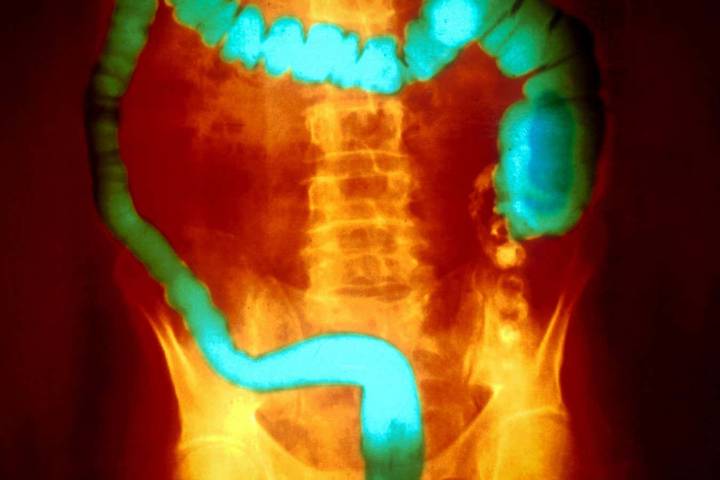

The discovery that a toxin made by bacteria found in dirty water might help trigger ulcerative colitis could lead to new treatments for this form of IBD